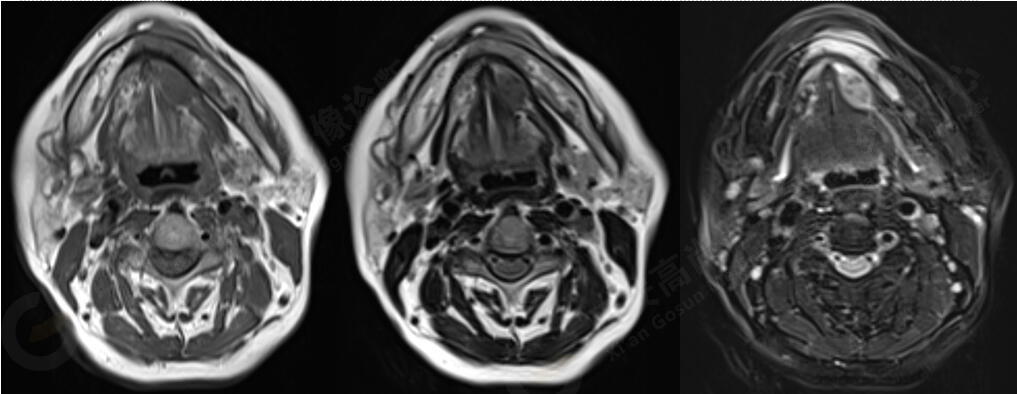

MR影像圖

MR平掃+增強:左側口底部下頜骨周圍見大小約3.4cmX3.3cmX3.3cm的團塊狀稍長T1稍長T2信號,壓脂像上呈稍高信號,病灶邊緣清晰,形態(tài)不規(guī)則,下頜骨骨質破壞,強化掃描示:左側下頜骨周圍病灶呈不均勻明顯強化,邊緣強化為著。

左側口底部下頜骨周圍占位,鱗Ca可能。

此腫瘤位于左側口底部下頜骨周圍,未見明顯囊變,下頜骨骨質破壞,DWI像上病灶呈明顯低信號,ADC圖上呈低信號,增強后不均勻明顯強化,病人年齡較大,可以考慮惡性腫瘤,口底好發(fā)鱗癌。